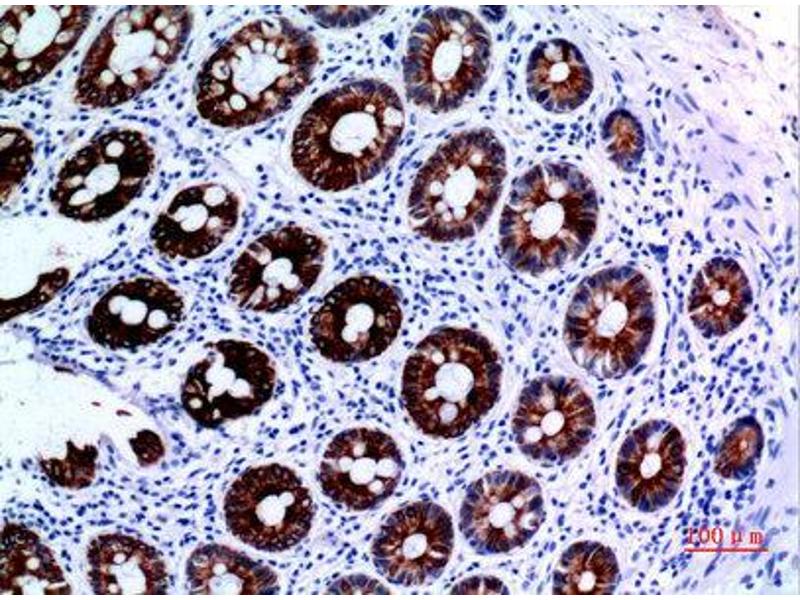

L'immunohistochimie (IHC) désigne le processus de détection des antigènes dans les cellules d'une coupe de tissu en exploitant le principe de liaison spécifique des anticorps aux antigènes des tissus biologiques. Elle est largement utilisée dans le diagnostic des cellules anormales comme celles que l'on trouve dans les tumeurs cancéreuses et dans la recherche fondamentale pour comprendre la distribution et la localisation des biomarqueurs et des protéines exprimées de manière différentielle dans différentes parties d'un tissu biologique. Visualiser une interaction anticorps-antigène peut être accompli de plusieurs façons. Dans le cas le plus courant, un anticorps est conjugué à une enzyme, comme la peroxydase, qui peut catalyser une réaction produisant une couleur, ou marqué à un fluorophore.